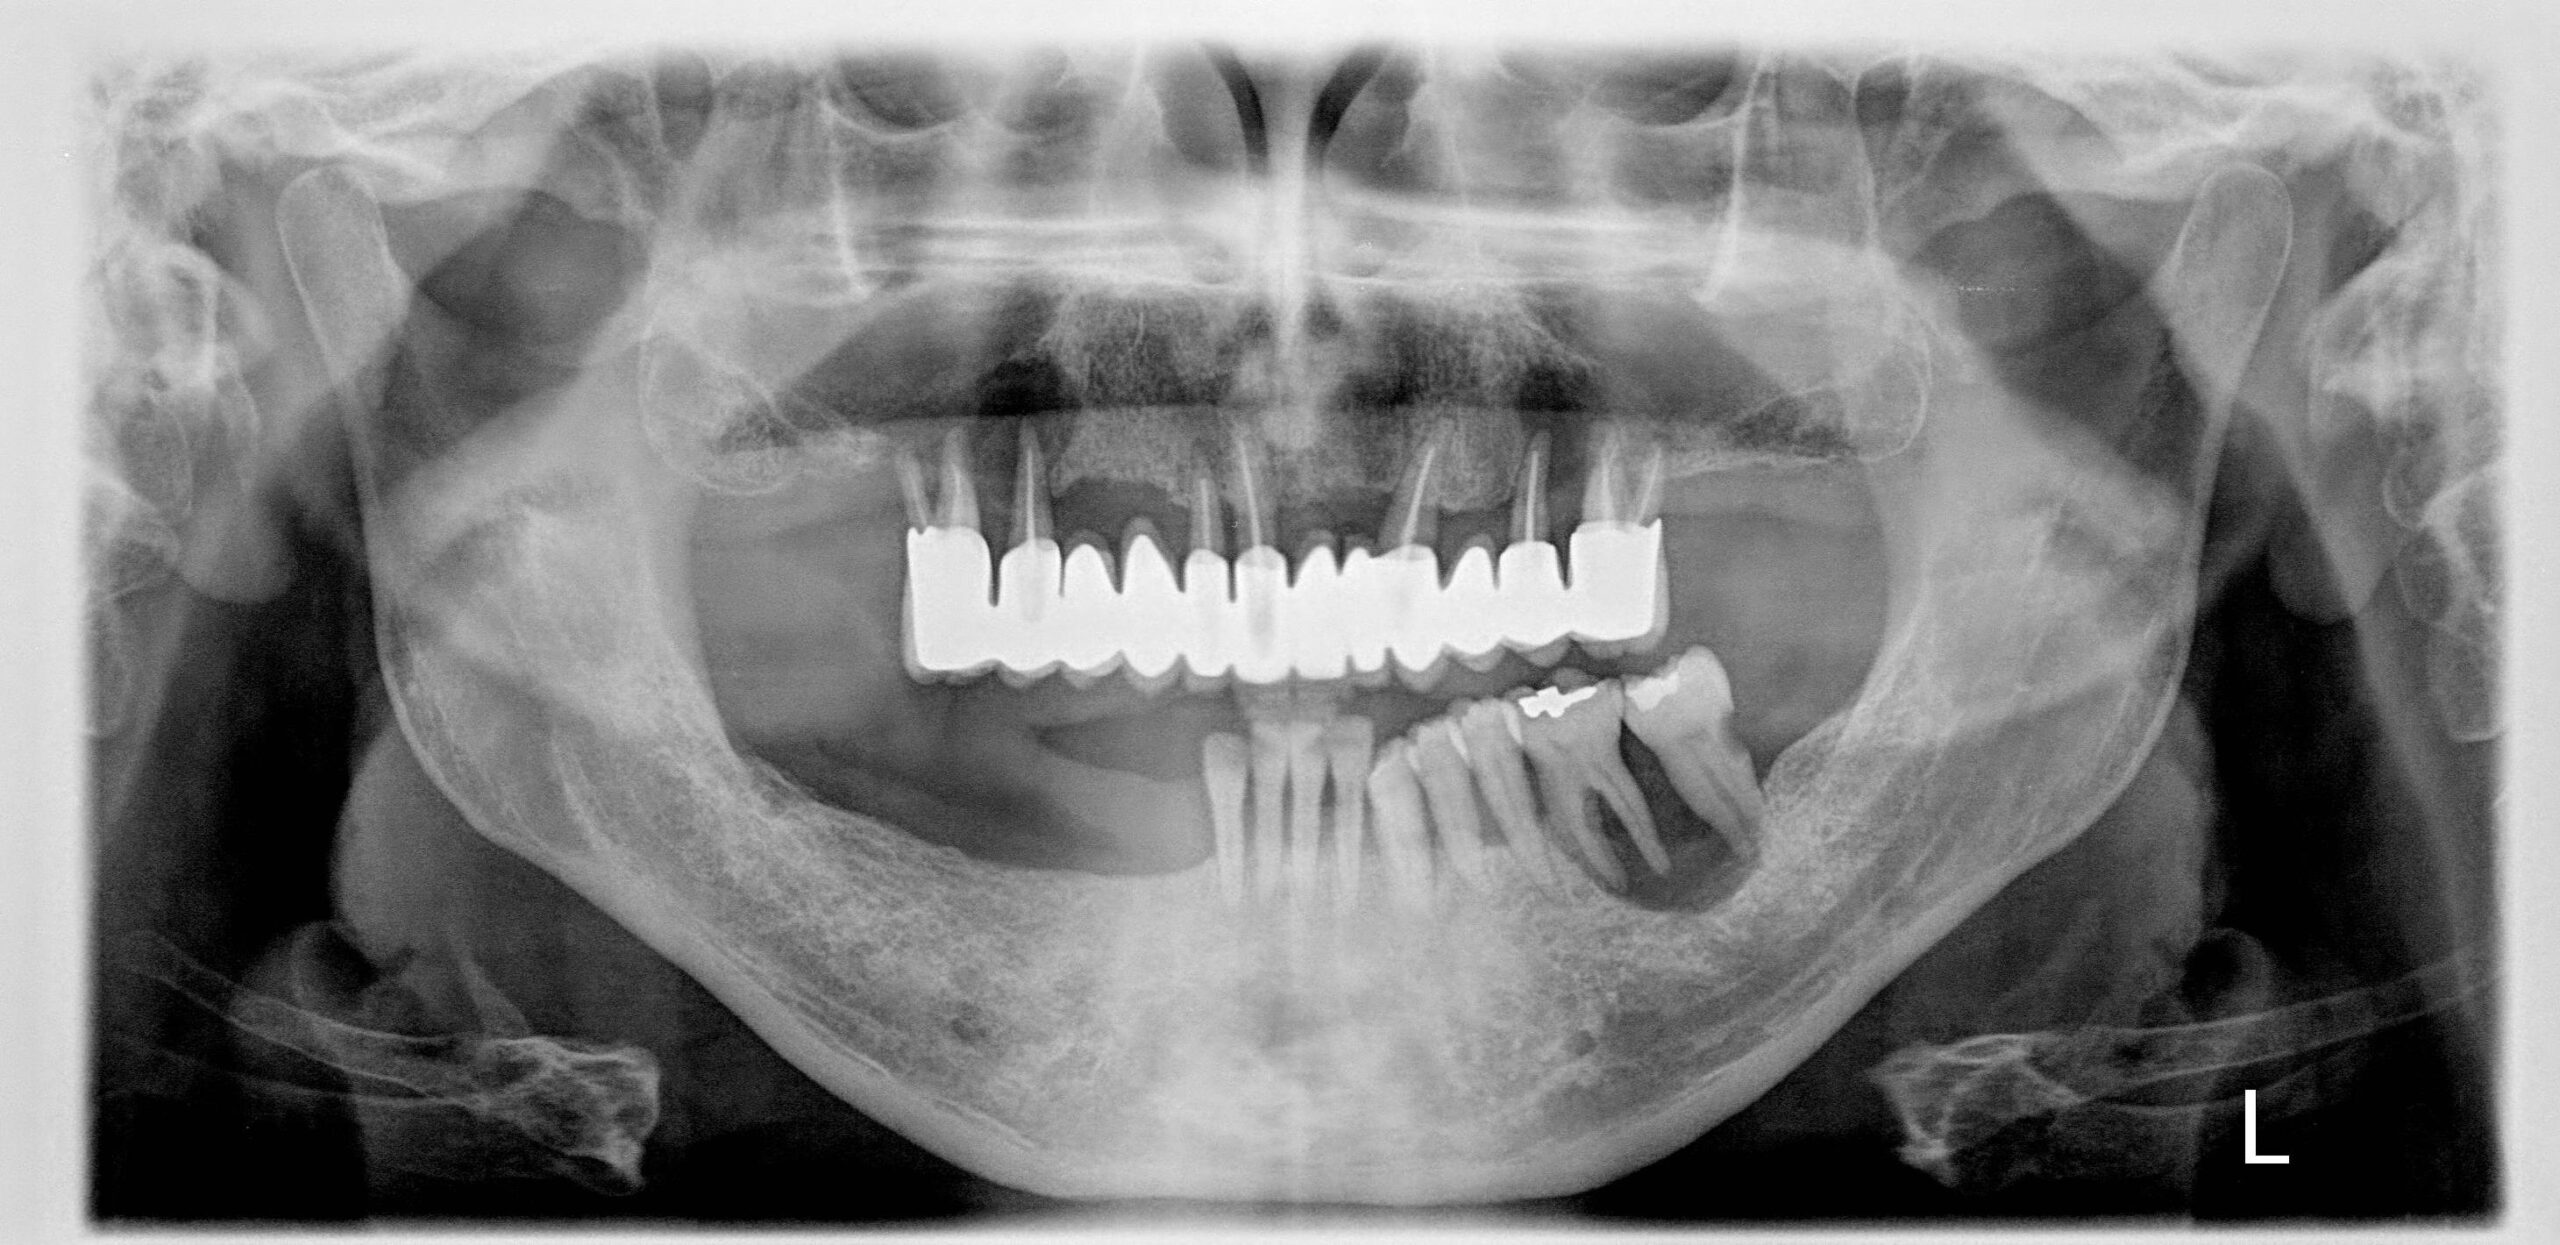

- Ακτινογραφικά εμφανίζεται σαν μονόχωρη διαύγαση, με σαφή ή κάπως ασαφή όρια που εντοπίζεται ακρορριζικά ή περιρριζικά των δοντιών με ζωντανό πολφό. Οι διαστάσεις των διαυγάσεων, φτάνουν τα 1-2 cm σε διάμετρο, αλλά σε αρκετές περιπτώσεις, είναι μεγαλύτερες. Με την υπολογιστική τομογραφία διαπιστώνεται η ύπαρξη οστεολυτικών αλλοιώσεων συνήθως πολλαπλών με ασαφή και σκοροφαγωμένα όρια, διάτρηση και λύση των φλοιωδών πετάλων της γνάθου ή του εδάφους του ιγμορείου άντρου και επέκταση της αλλοίωσης στους παρακείμενους ιστούς.

- Κλινικά το ηωσινόφιλο κοκκίωμα, εμφανίζεται πολύ συχνά, με εικόνα νόσου του περιοδοντίου. Συνήθως, τα παρακείμενα με την εστία της νόσου δόντια, παρουσιάζουν ευσειστότητα και σε προχωρημένα στάδια αποπίπτουν.